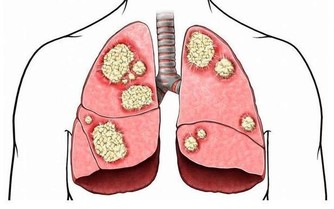

主要是生活方式不良,造成代謝紊亂的病理狀態,增加患上心臟疾病、脂肪肝和嚴重癌症的風險。